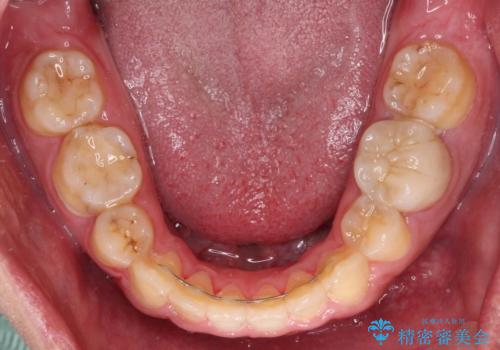

後戻りでデコボコの前歯 インビザライン矯正治療

下顎骨が左側に変位しているため、正中が合わないことは予想できましたが、歯列が整った後も咬み合わせが安定せず、咬み合わせを落ち着かせるために1年以上の期間を要しました。

噛みにくさの改善に時間がかかってしまうことがインビザラインの欠点の1つといえます。